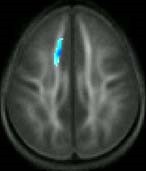

The area of lower quality white matter (blue area) among poor readers relative to good readers at the beginning of the study. Source: Timothy Keller, Ph.D.; Marcel Just, Ph.D.

At the outset of the study, poor readers showed lower quality white matter than average readers in a brain region called the anterior left centrum semiovale. Six months later, at the completion of the intensive training, the poor readers showed significant increases in the quality of this region. Children who did not receive the training did not show this increase, suggesting that the changes seen in the remedial training group were not due to natural maturation of the brain.